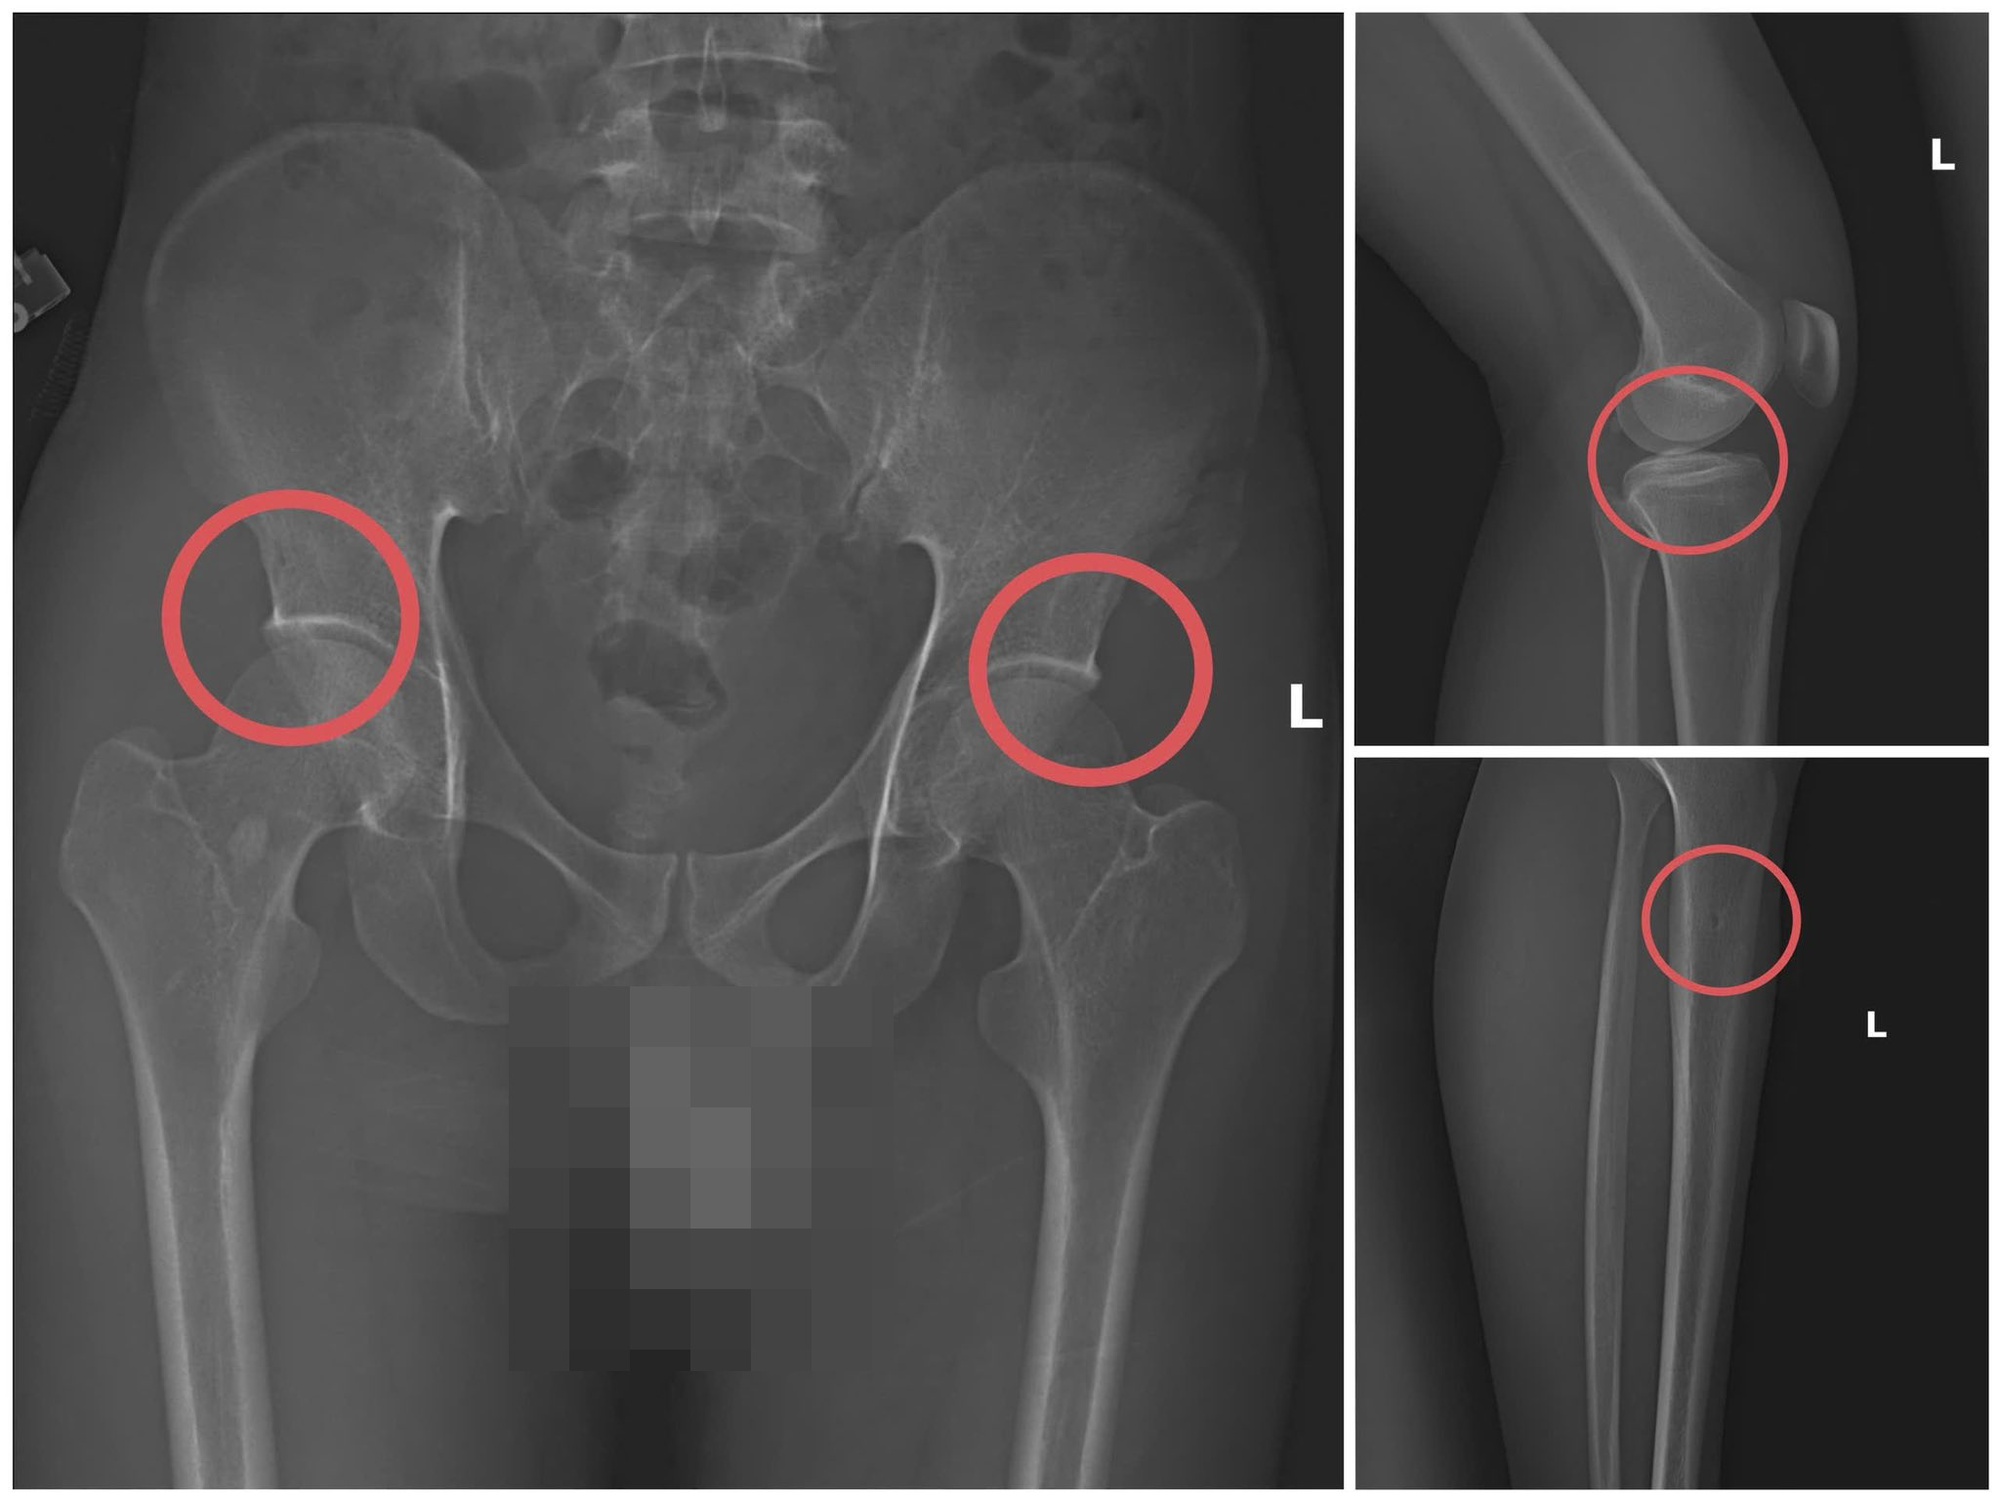

Hình ảnh xương khớp do Châu gây thương tích để chiếm đoạt tiền bảo hiểm nhân thọ – Ảnh: Công an tỉnh Phú Thọ

Với thủ đoạn trên, các đối tượng đã chiếm đoạt hơn 6 tỷ đồng từ nhiều công ty bảo hiểm nhân thọ như Manulife, AIA, Dai-ichi Life, FWD, Sun Life, Chubb Life… riêng Công ty Manulife bị chiếm đoạt 2,6 tỷ đồng.